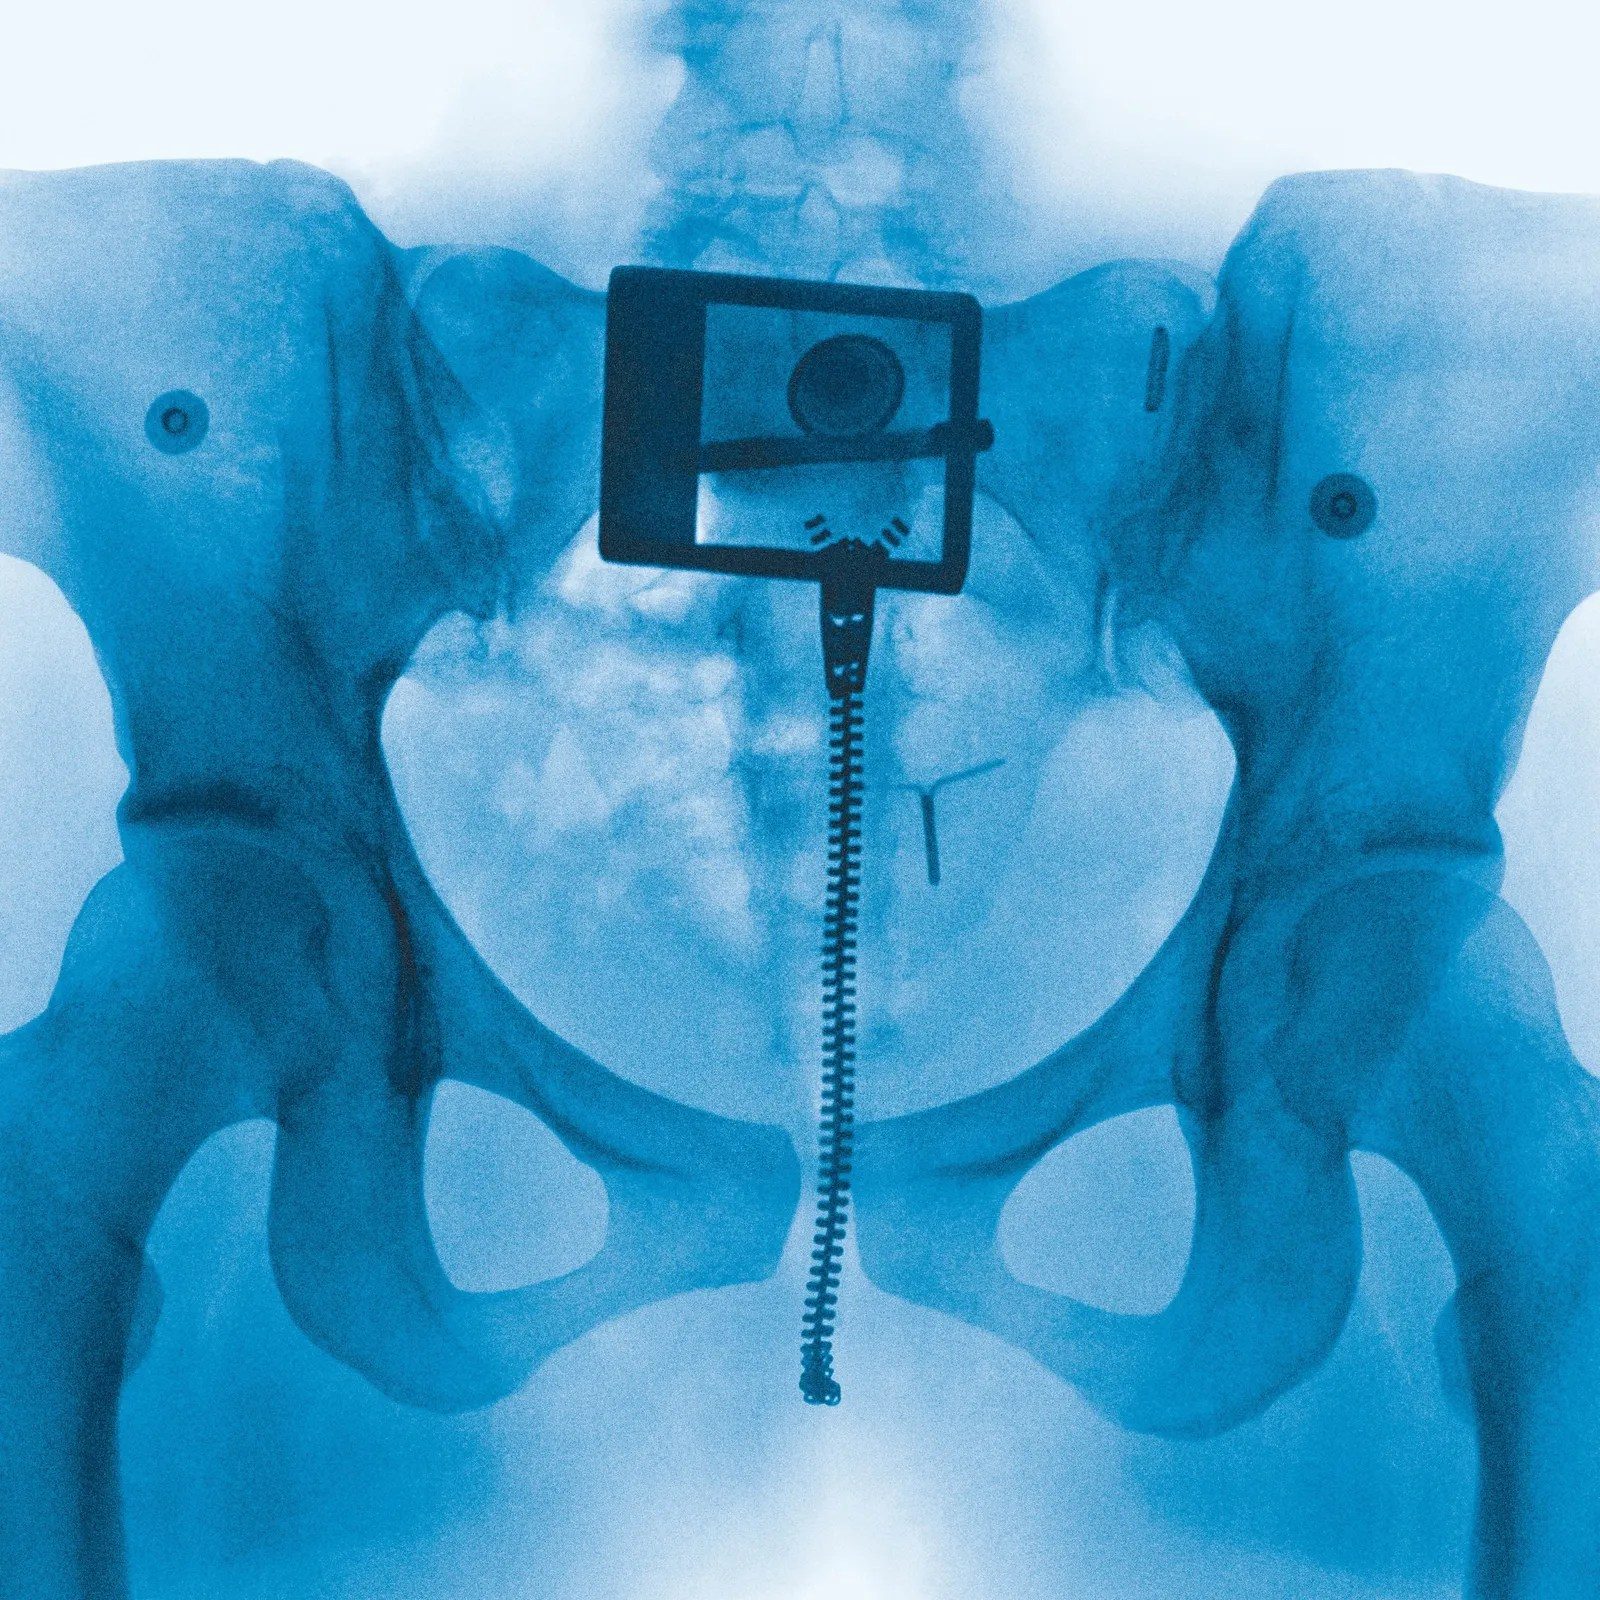

Un creador de TikTok planteó la hipótesis de que la falta de una capa de etiqueta impresa en el CD transparente puede estar confundiendo a los sensores ópticos más antiguos, que normalmente dependen de los reflejos y los patrones de luz para leer los discos. Hasta ahora, el equipo de Lorde no ha abordado públicamente el tema.